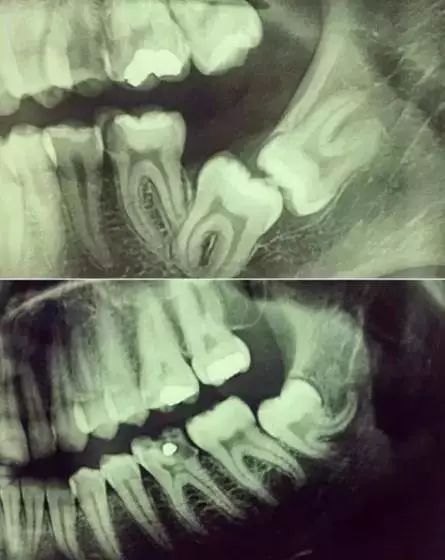

從下圖可以知道除了外層嘅一點牙釉質,牙齒裏面出咗問題,肉眼係睇唔到嘅。牙醫唔係有透視眼。所以,為咗全面咁了解牙齒,拍張牙片仲係好有必要嘅。

齒根係埋喺齒槽骨入邊嘅,醫生冇透視眼,為咗了解受損牙齒嘅牙根形態同方向、帶住、長度同埋根尖附近有冇病變或者大小,或者懷疑有啲肉眼睇唔到嘅牙科問題,都會建議患者去牙科X照,甚至,口腔CT嚟全面性地確認問題,去制定啱啱嘅治療計劃。